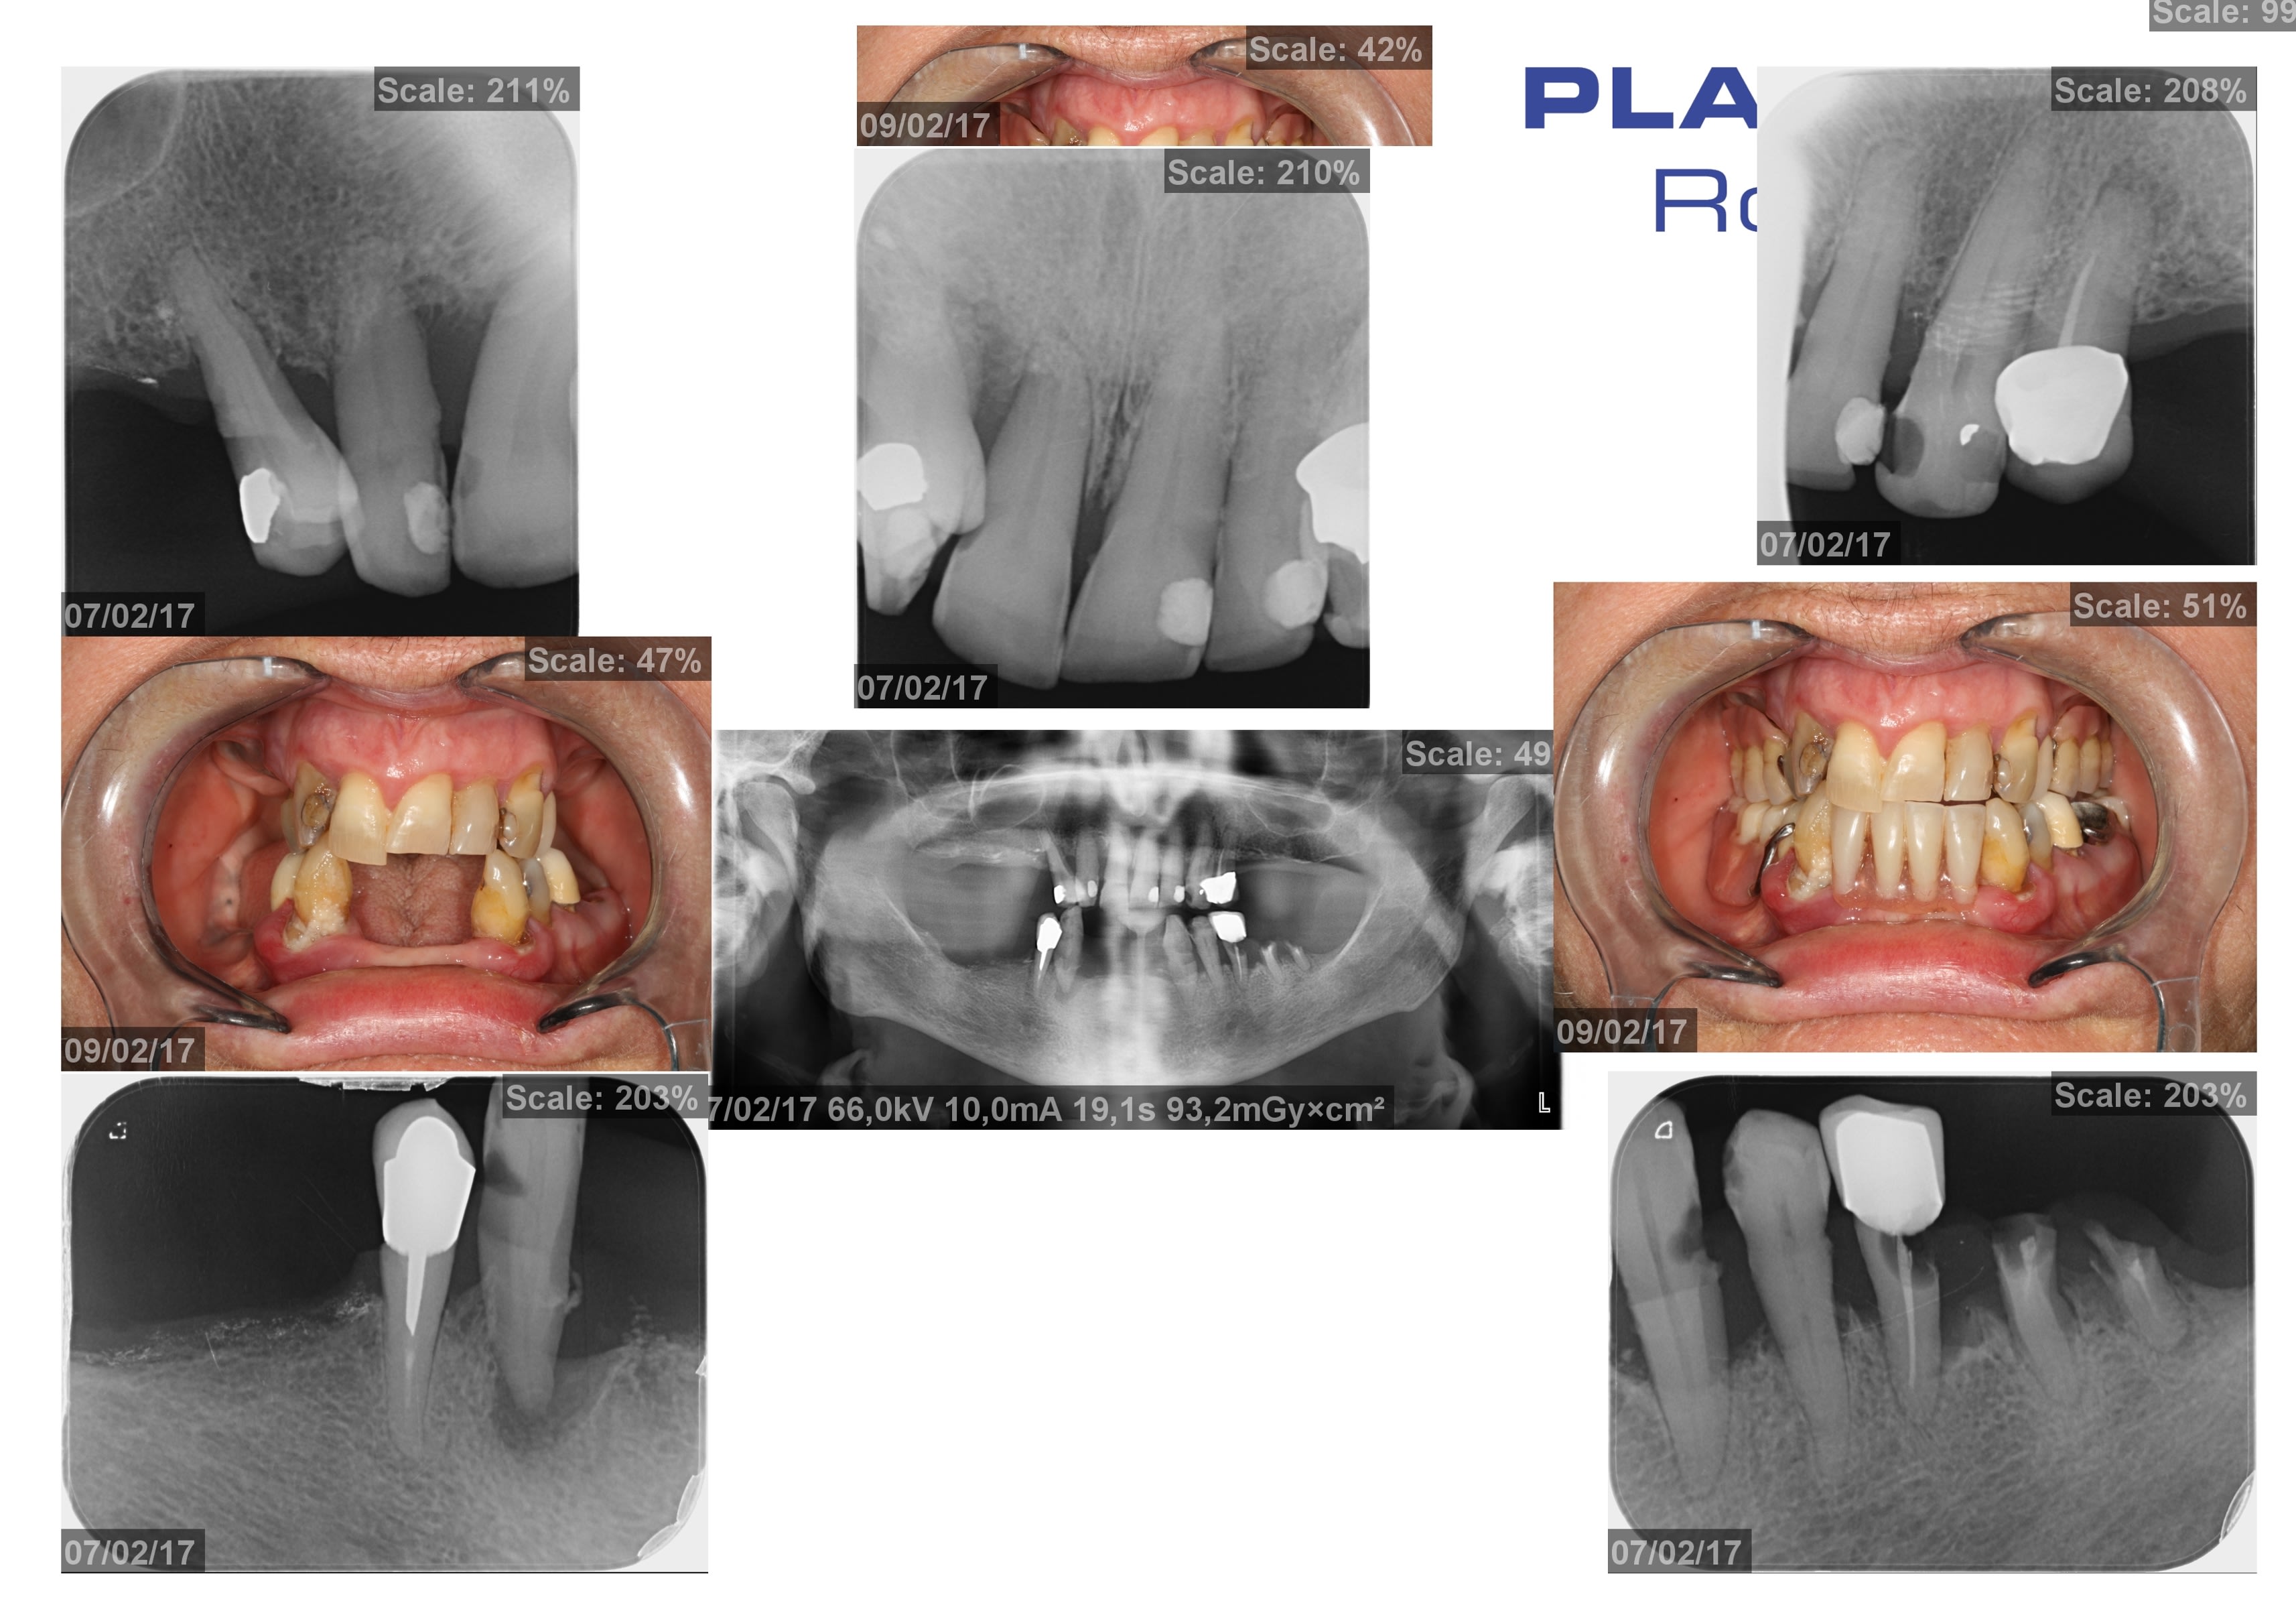

Bonjour à tous. J'ai un cas intéressant : patiente 78 ans bon état général qui viens car à des dents infectées et n'a jamais été satisfaite de ses prothèse amovibles partielles.....

C'est de toute évidence une bonne indication de prothèse sur implant et chance le capital osseux est plutôt pas mal.

Vous la géreriez comment vous ? All on 4 / All on six traditionnel, ou plus d'implant en particulier postérieurs ? surtout pour le bas pensez vous qu'un bridge complet avec des implants en arrière du foramen soit contre indiqué (flexion mandibule...).